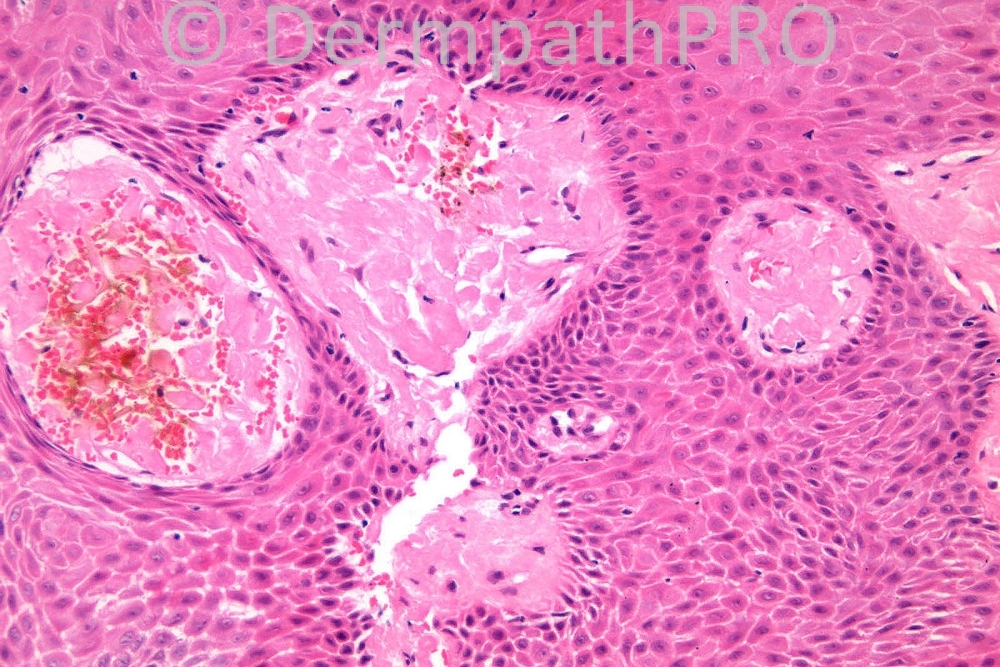

Male 84 years, tight anal stenosis, with sclerotic appearance.